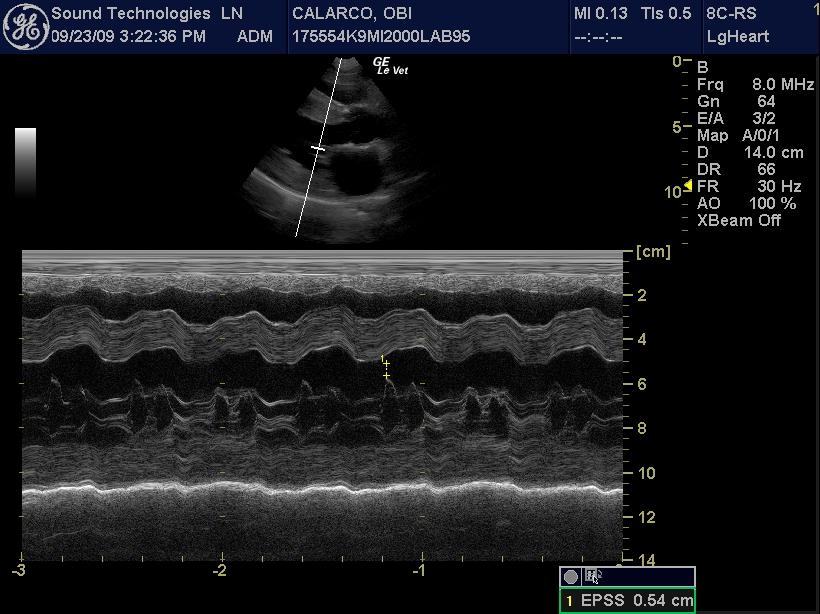

An 11-year-old MN Labrador retriever was prestented for excercise intolerance, lethargy, depression, vomiting and diarrhea. The physical exam was unremarkable other than a grade 2 left sided heart mumur at the heart base and irregular heart beat with pulse deficits. CBC, CHEM, UA, and acth stim were all normal.